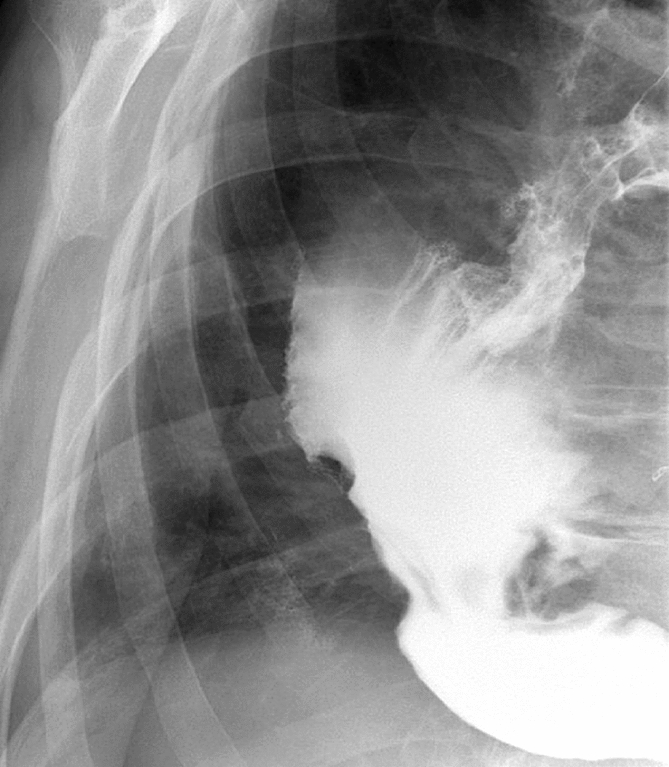

M. Carolina Jimenez, MD; Robert F. Cubas, MD; Jose M. Martinez, MD; University of Miami/Jackson Health System

Introduction: Biologic mesh has been used in clean-contaminated and contaminated fields and while wound infection rates may be high, infection is usually superficial and graft removal is unusual. Biologic mesh has been reported to have higher recurrence rates and poor incorporation into native tissue in comparison to synthetic mesh. Currently, there is no consensus on mesh preservation treatment in cases of mesh infection after hernia repair.

Methods: We present a 72-year-old male with prior radical cystectomy and neobladder creation complicated at the time by neobladder-cutaneous fistula and wound infection requiring revisional surgery and incisional hernia repair with mesh. He developed a large recurrent incisional hernia and underwent open hernia repair with bilateral anterior component separation, extensive lysis of adhesions, removal of prior mesh, and placement of a biologic mesh (Strattice™ RTM) in an underlay and onlay fashion. Intraoperatively, the defect measured 20 cm long by 14 cm wide. Postoperatively, he was treated for neobladder infection and CT cystogram found no extravasation from the neobladder. He presented to the emergency department 6 weeks after surgery with spontaneous partial midline wound dehiscence, with exposure of the onlay mesh and drainage of clear fluid, which was confirmed to be urine by fluid creatinine level. Repeat CT scan demonstrated a filling defect at the anterior wall of the neobladder with contrast leaking into a contained collection interposed between the anterior abdominal wall and the underlay mesh, extending superiorly between the small bowel loops and dehiscence of the midline abdominal wound. The patient was treated with a course of antibiotics and indwelling Foley catheter and bilateral nephrostomy tubes for urine diversion.

Results: Three months later, repeat CT cystogram demonstrated resolution of the leak and the nephrostomy tubes and Foley catheter were removed. The patient has continued daily wound care with significant reduction in size of the midline wound and increasing granulation tissue around the onlay mesh. He has not required further admissions to hospital and there has been no hernia recurrence so far.

Conclusion: In the appropriate setting, contaminated biologic mesh after surgery may be treated with medical management with adequate wound closure, avoiding the need for surgery and mesh explantation.